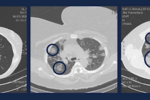

Koronawirus jest już w Polsce. Co można robić i jak się zabezpieczać przed wirusem Sars-CoV-2? Kiedy i komu jest potrzebna maseczka na twarz?

Rzadko słyszymy o tym, że zarażeniu się wirusem Sars-CoV-2 uległo dziecko. Z jednej strony eksperci zastanawiają się, dlaczego tak się dzieje, z drugiej cieszą się, ponieważ jest szansa na szybsze wygaszenie epidemii.